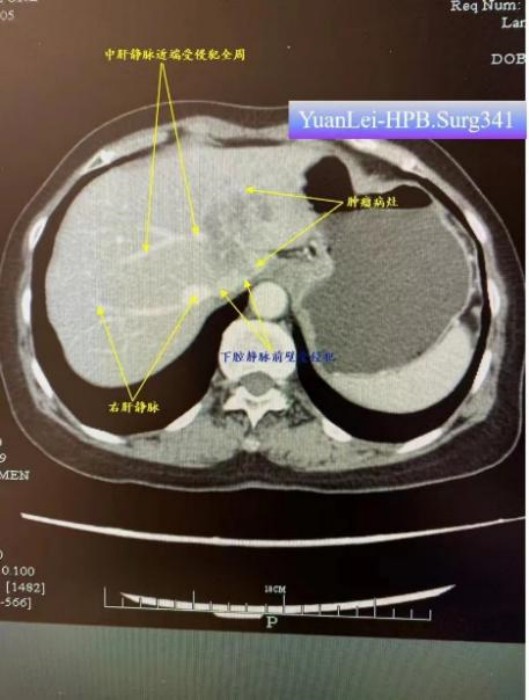

來(lái)自衢州市龍游縣68歲的藍(lán)阿姨,因腹痛去醫(yī)院檢查,診斷為左肝及尾狀葉肝內(nèi)膽管癌,侵犯中肝靜脈近端主干360度、侵犯下腔靜脈。因手術(shù)風(fēng)險(xiǎn)大,從當(dāng)?shù)蒯t(yī)院慕名轉(zhuǎn)入袁磊團(tuán)隊(duì)進(jìn)行手術(shù),袁磊組織團(tuán)隊(duì)進(jìn)行術(shù)前討論,制定了詳細(xì)的手術(shù)方案和風(fēng)險(xiǎn)防范措施,術(shù)前即擬定了全肝血流阻斷方案。術(shù)中在下腔靜脈受侵的部位處理時(shí),憑借高超的手術(shù)技術(shù)和過(guò)人膽識(shí),袁磊果斷實(shí)施全肝血流阻斷,切除受侵部分下腔靜脈前壁,從容修補(bǔ)靜脈壁缺損,成功完成了解剖性肝左三葉+全尾葉切除術(shù)+下腔靜脈壁修補(bǔ)+區(qū)域淋巴結(jié)清掃+膽囊切除術(shù)。